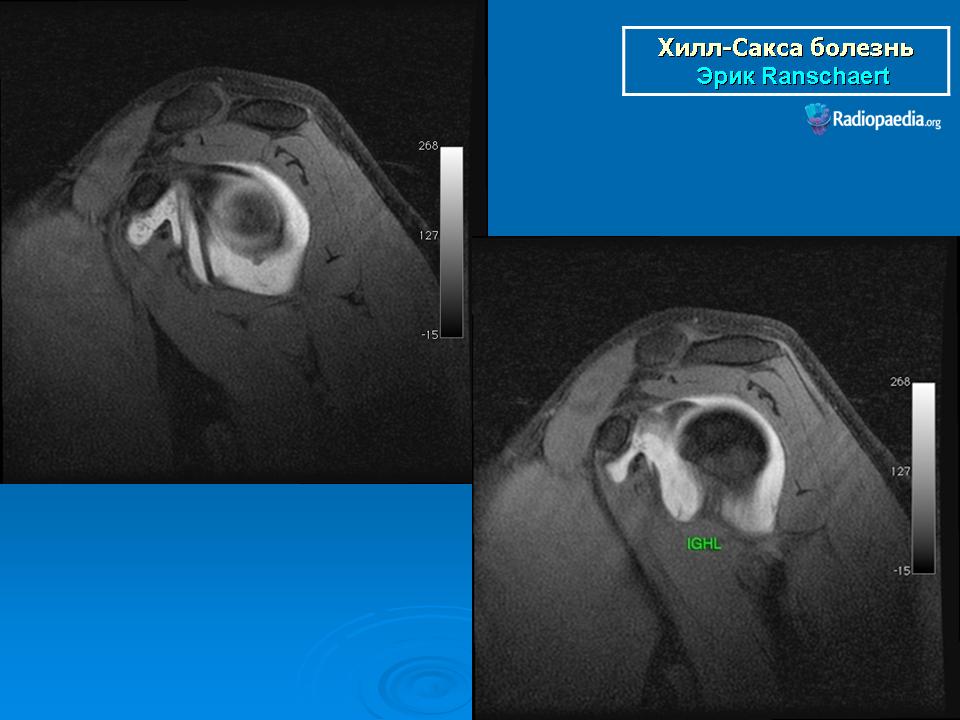

На рентгенограмме плечевого сустава определяется умеренный остеопороз головки плечевой кости. Иногда на ее задненаружной поверхности позади вершины большого бугорка выявляется вдавленный дефект (повреждение Хилл-Сакса). Дефект четко виден на рентгенограмме в аксиальной проекции. Аналогичный, но менее выраженный дефект может быть выявлен в зоне передненаружного края суставной впадины лопатки. Также в диагностике причин привычного вывиха плеча помогает МРТ исследование.

рентгенограмма плечевого сустава. Повреждение Хилл-Сакса и сопутствующий кальциноз сухожилий вращательной манжеты